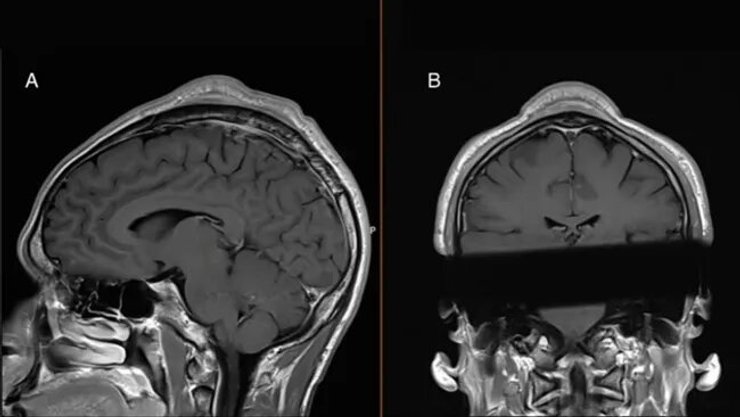

Медики дослідили опуклість і провели структурне сканування черепа та встановили, що між шкірою та черепом була затиснута м’яка маса, а також те, що шкіра над пухлиною та кістка під нею були значно товщі, ніж тканини, що оточують череп.